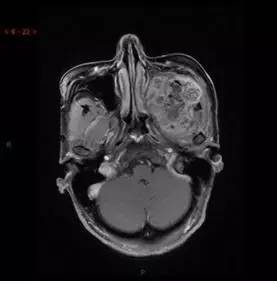

T2WI/FS轴位

解析:本病例为中颅窝至颞下窝沟通性病变,对周围骨质主要呈膨胀压迫性改变,伴囊变、出血。

病理:(中颅底内外沟通肿瘤) 神经鞘瘤,伴出血,局灶细胞较丰富。免疫组化结果显示:EMA(-), P53(-), S100(3 ), NF(-), PR(-), desmin(-), Ki-67( ,5-10%)